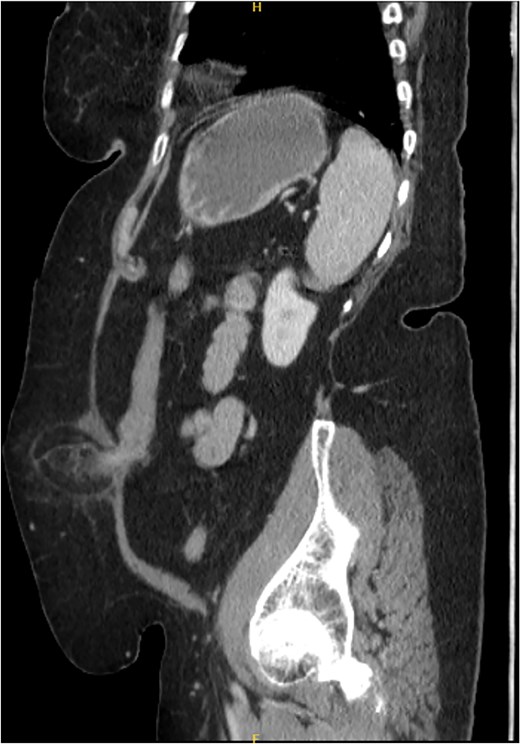

A 76-year-old female with a medical history of type 2 diabetes mellitus (controlled with oral medications), hypertension (on two medications), hyperlipidemia (on atorvastatin), and recently diagnosed Alzheimer’s disease (started on memantine) presented to the emergency department with severe left-sided abdominal pain of 2 days’ duration. The pain began gradually but worsened significantly in the last few hours. It was associated with a bulging mass in the abdomen that was tender and painful to touch. The patient reported that the swelling had been present for 2 years, intermittently reducible with minimal exertion. However, since the previous day, it had become irreducible and increasingly painful, particularly after a failed attempt to reduce it manually at home. She also admitted to chronic constipation for years, usually treated with oral laxatives, though she had not been compliant with them recently. Her surgical history included a laparoscopic cholecystectomy combined with paraumbilical hernia repair using mesh 3 years ago. Upon examination by the on-call surgical team, the patient was afebrile with stable vital signs. Her abdomen was distended, and a 7 × 7 cm irreducible, tender mass was noted over the left side. An urgent computed tomography (CT) scan of the abdomen and pelvis with intravenous and oral contrast revealed a left lateral ventral abdominal hernia traversing the left lateral oblique muscles. The hernia sac contained omental fat and an inflamed diverticulum of the transverse colon, with surrounding inflammatory changes. The defect measured 1.4 × 1 cm, and the hernia sac measured 6.7 × 4.2 × 4 cm. No free fluid, fluid collections, or pneumoperitoneum were identified (Figs 1–3).

Coronal section of CT abdomen and pelvis showing the ventral hernia.

Sagittal section of CT abdomen and pelvis showing the ventral hernia.